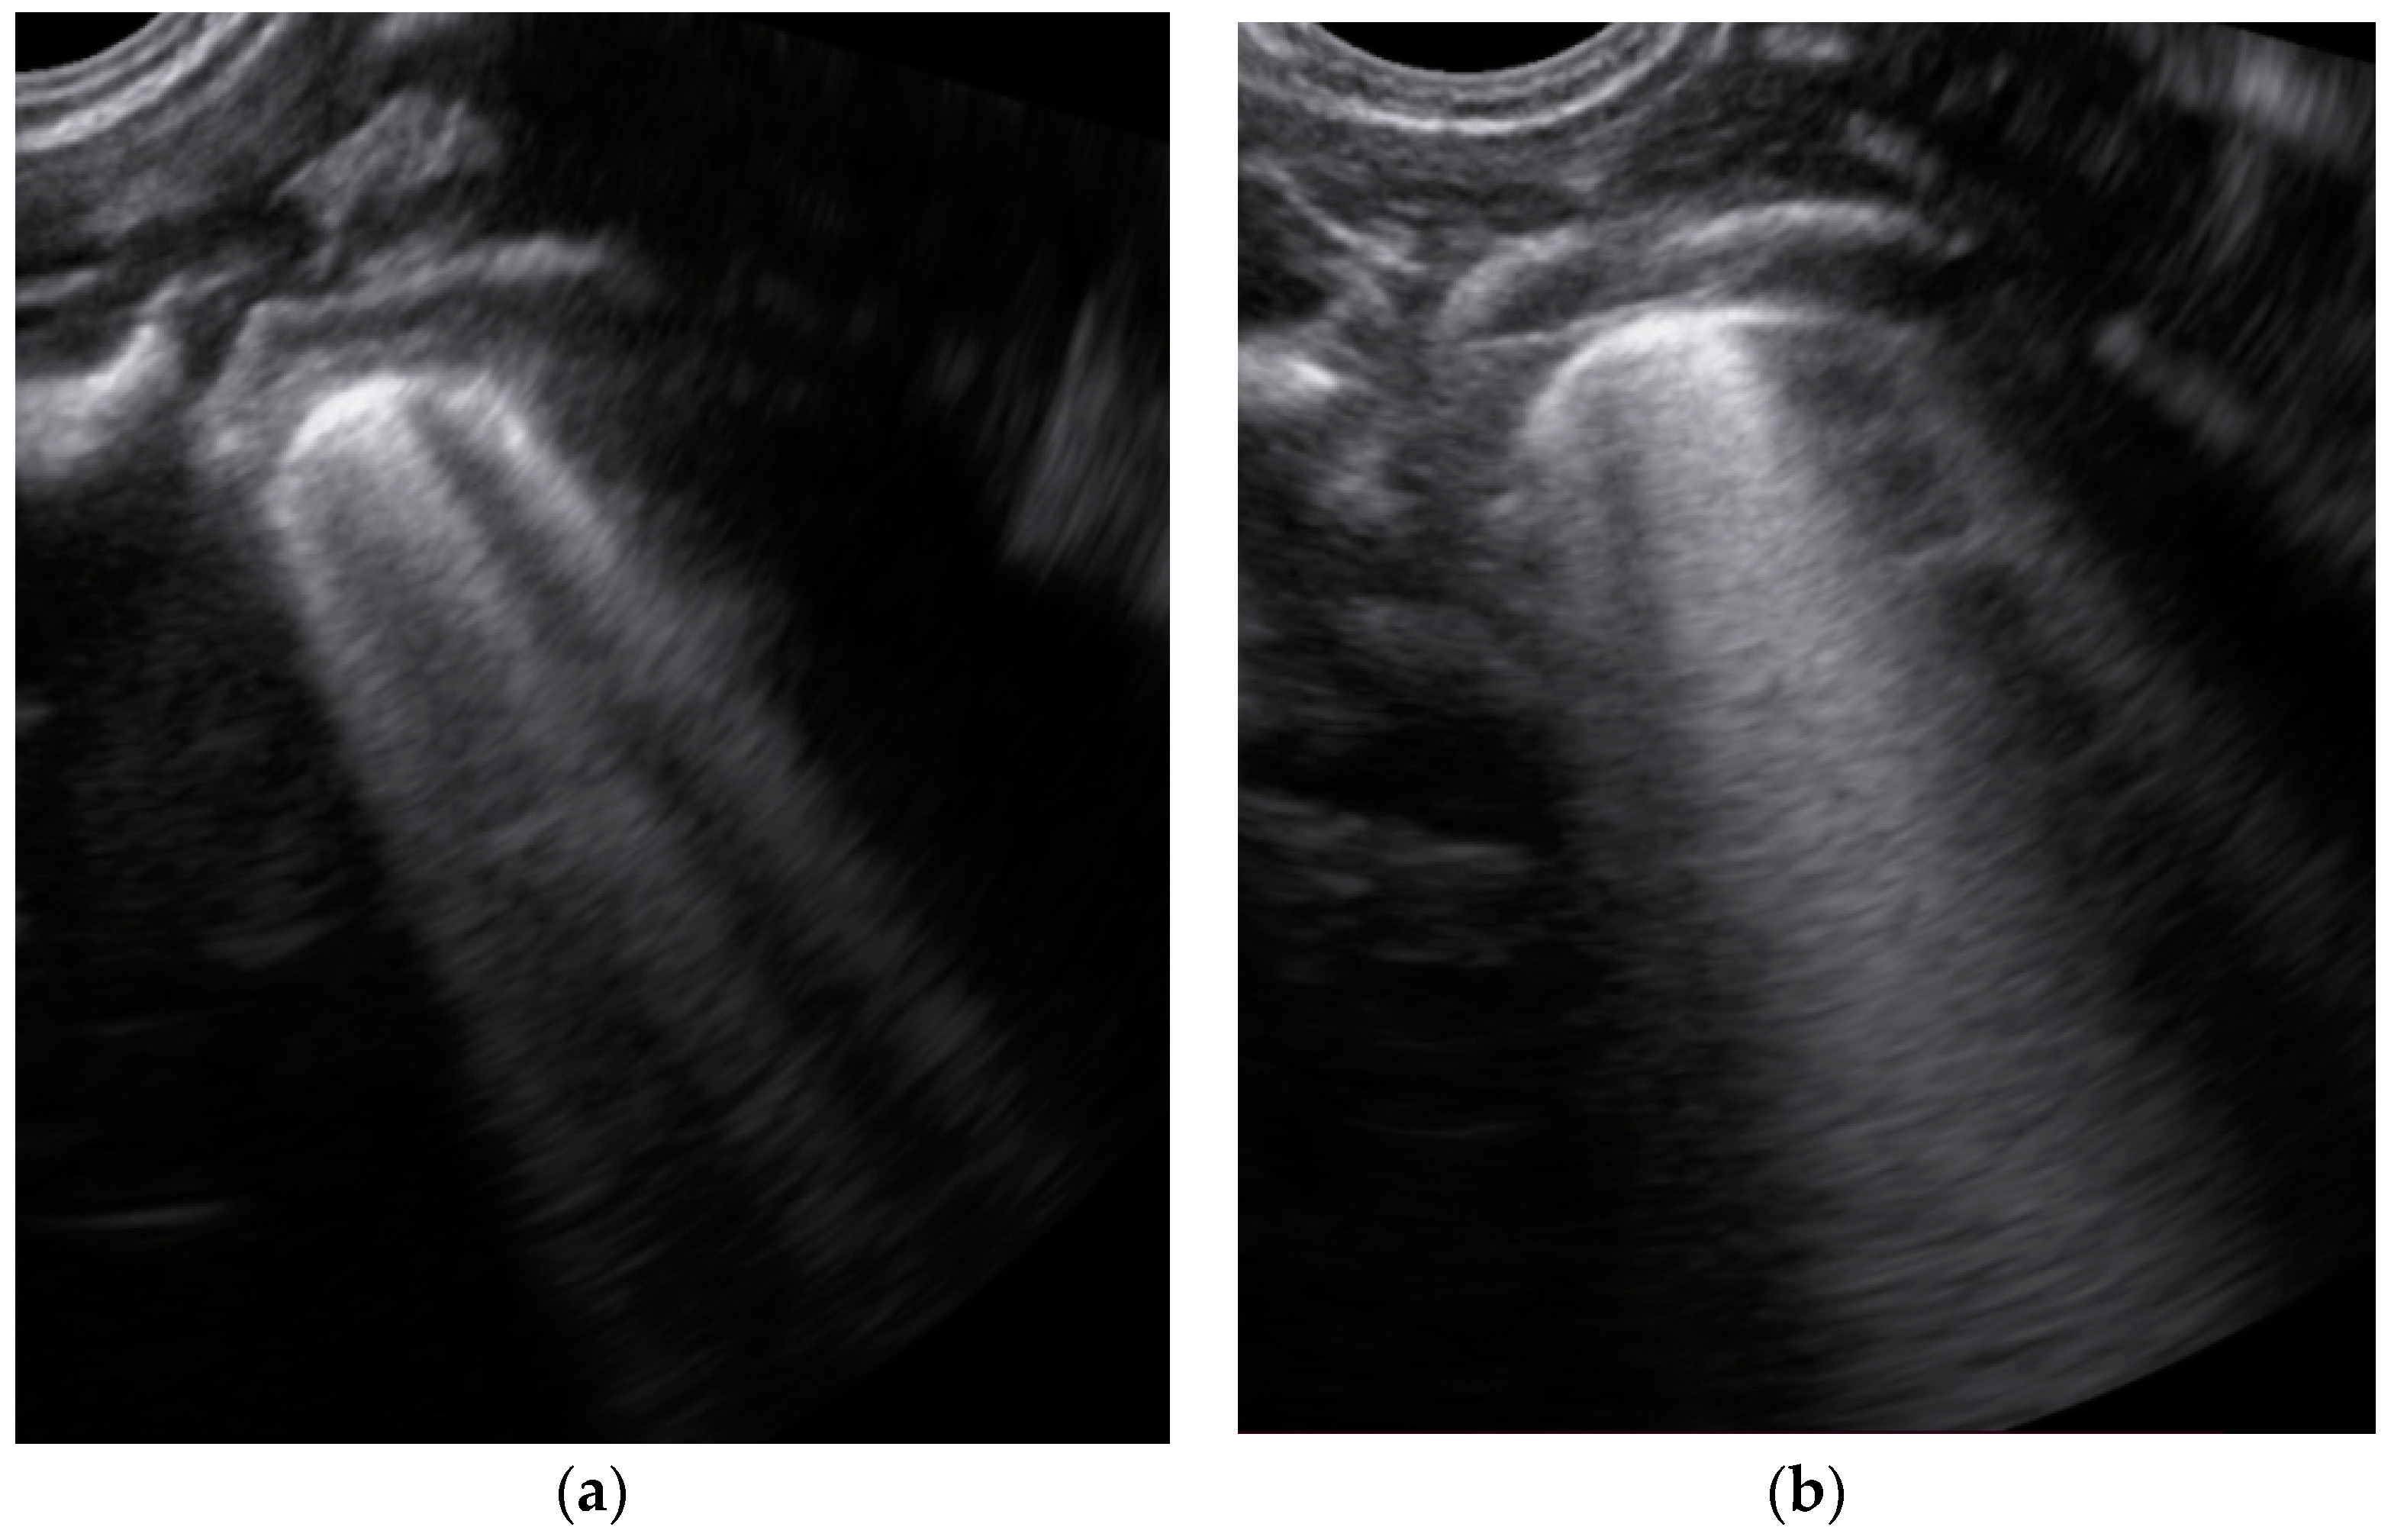

- Sparse B-lines (Figure 3a)—100%;

- Confluent or coalescent B-lines (Figure 3b)—57.89%;

| Description of images | Physiological A-lines (upper image) One or two B-lines per intercostal space (marked with yellow arrows) with smooth pleural line (lower image) | More than two B-lines per intercostal space with irregular or thickened pleura | Coalescent/confluent B-lines (upper image)/‘white lung’ or small subpleural consolidations (<1 cm—lower image) | Large consolidations (>1 cm) ± air bronchogram—the image is from a newborn not include in the study with bacterial pneumonia |